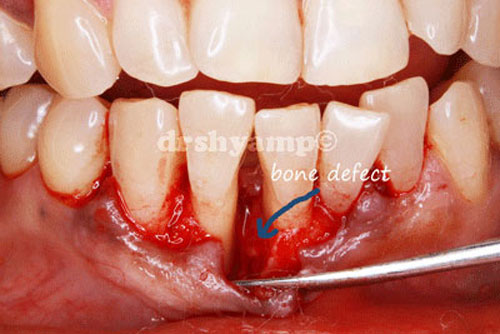

Bone grafting